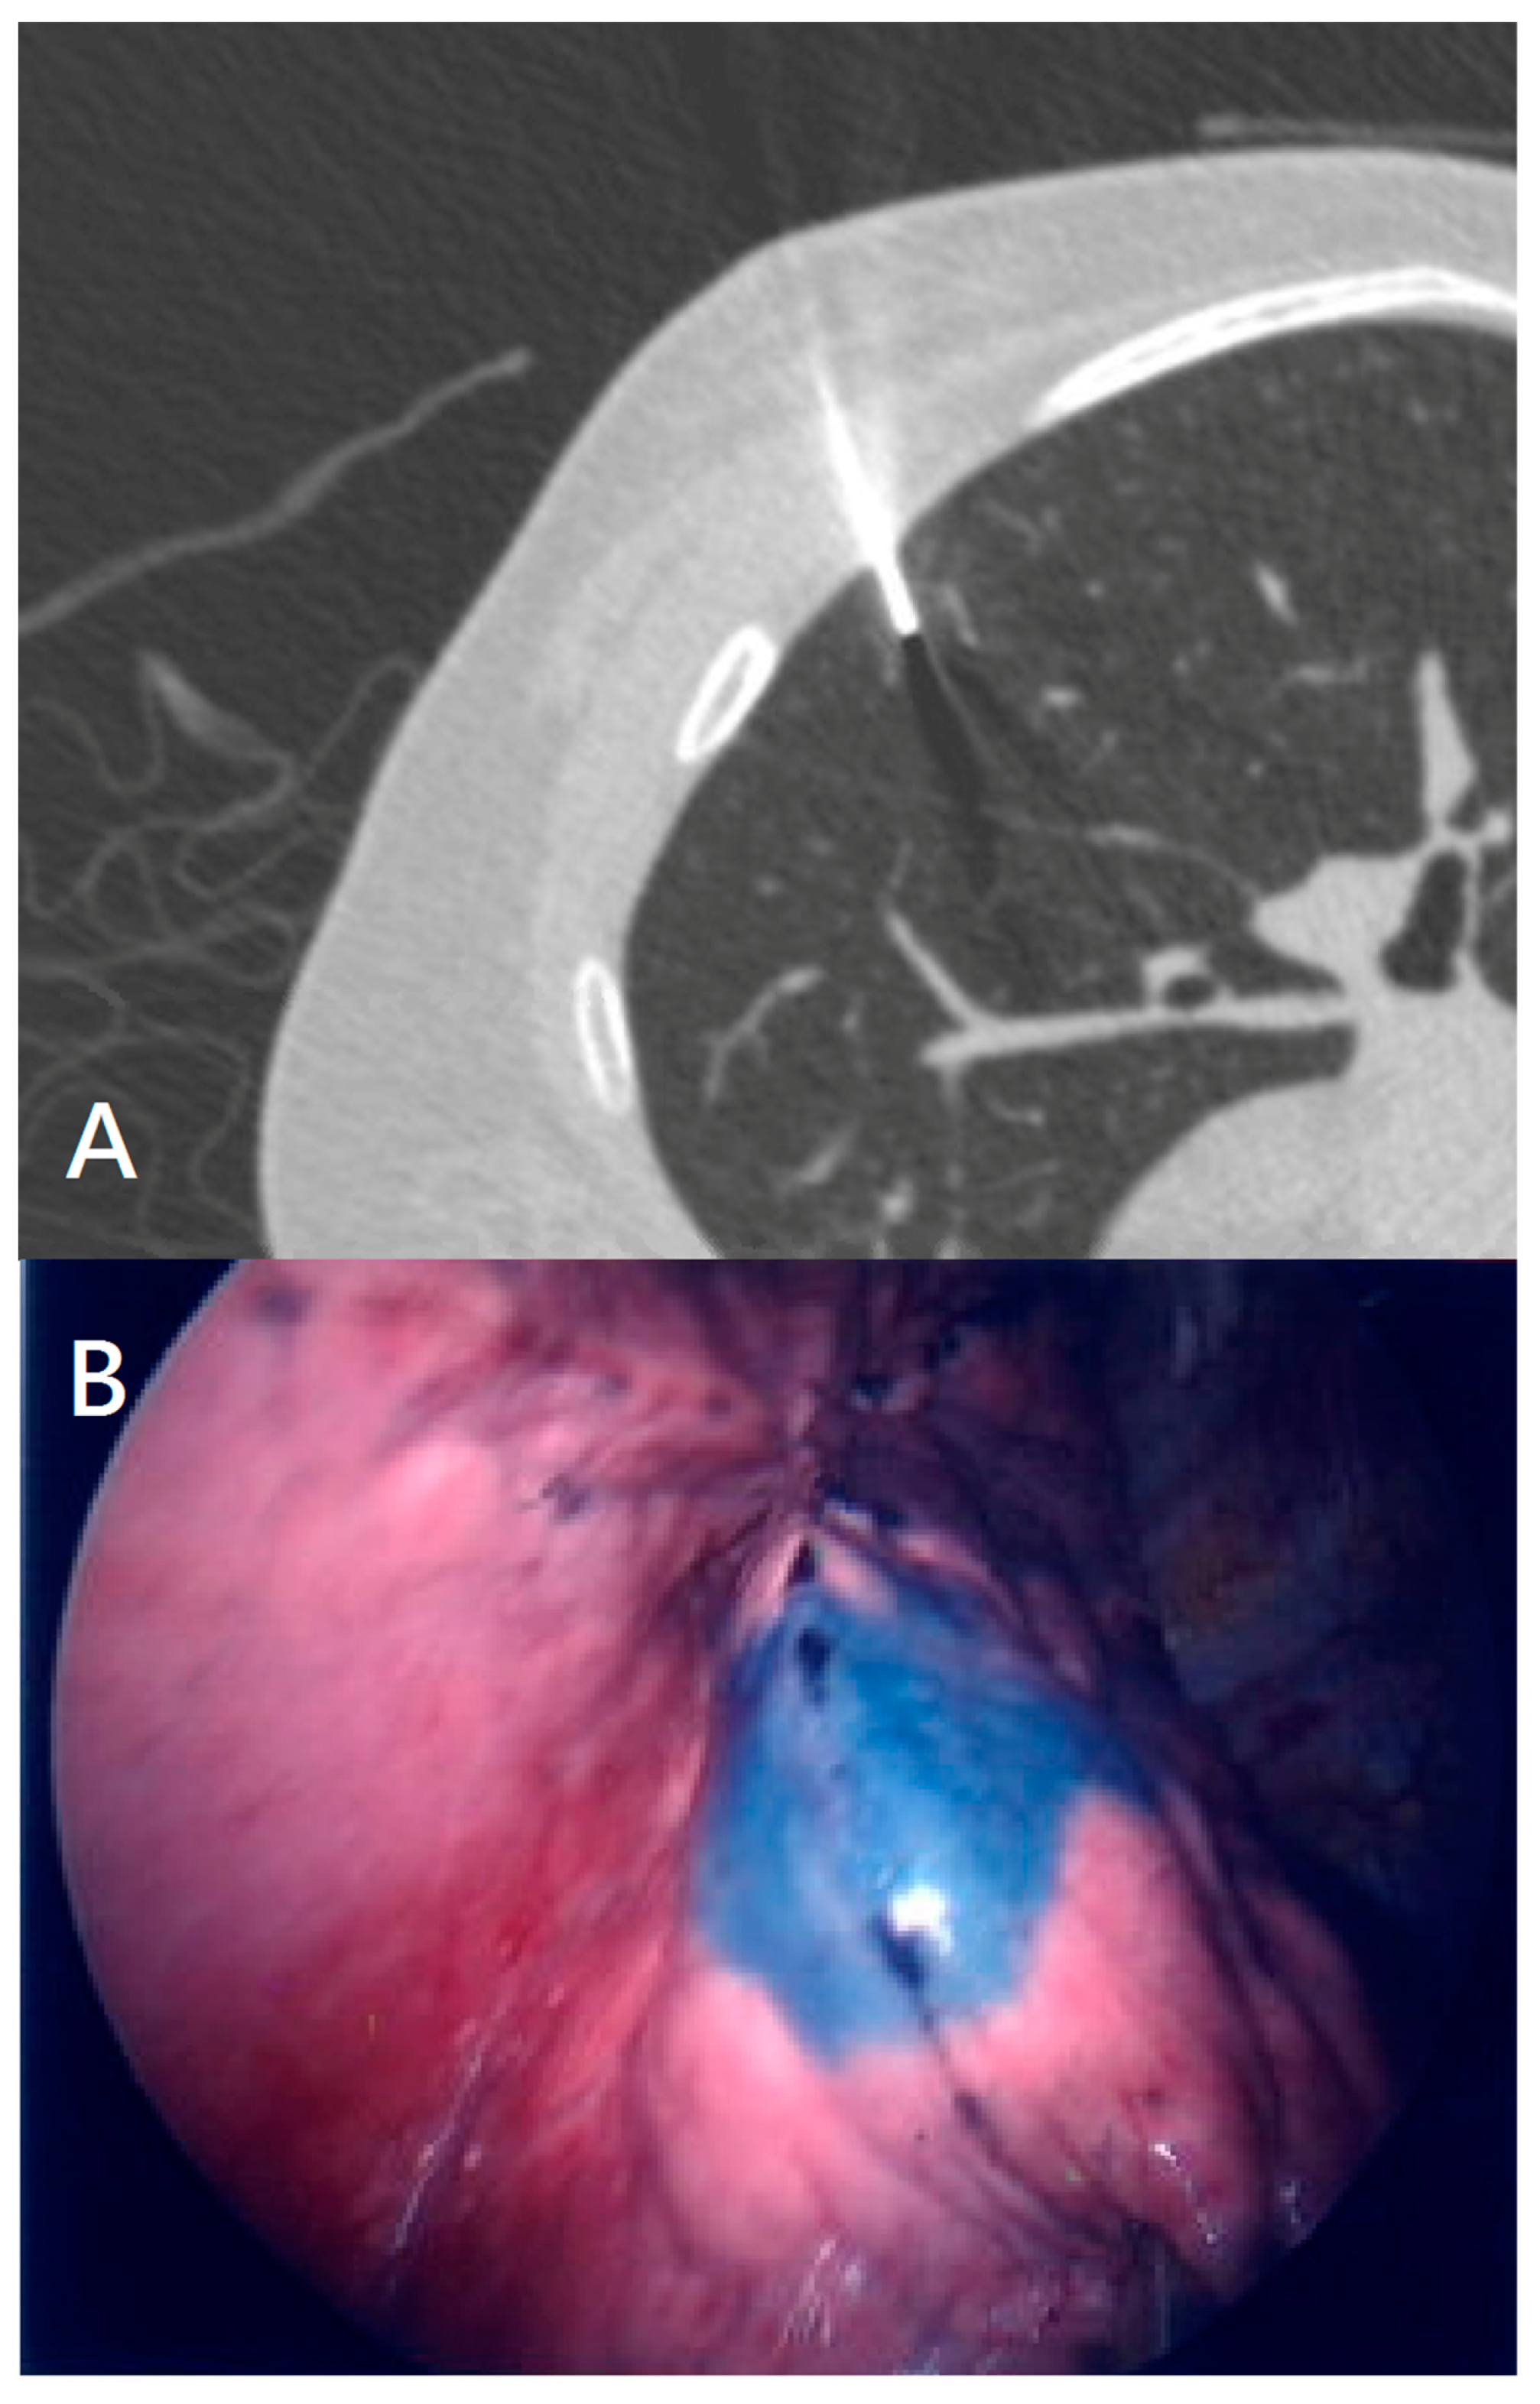

Patients underwent general anesthesia with or without intubation before all procedures. We used the computer console of a seventh-edition SuperDimension Navigation System (Covidien, Minneapolis, MN, USA) with planning software to localize and plan a route to the nodules one day prior to the operation. We used the best available exit point from the bronchial tree if no bronchus led to the nodule. Each nodule was localized with a locatable electromagnetic guide, the navigational console and an extended working catheter. The electromagnetic guide was removed after the nodule was located, while the extended working catheter was left in place. We used a bronchoscopic sprayer inserted through the extended working catheter, and injected patent blue vital (0.15 mL) into the nodule. We used an additional injection of no more than 0.15 mL patent blue vital to mark the pleural surface. The patient then was changed to lateral position following by VATS operation (Figure 1A,B).

Figure 1.

(A) ENB navigation for localization of the lung nodule; (B) ENB localization shows the lung tumor position by pleural marking during VATS.

Figure 2.

(A) CT-guided localization of fine-needle localization with PBV (Patent Blue Vital); (B) Pleural marking by CT-guided localization method revealed by VATS.